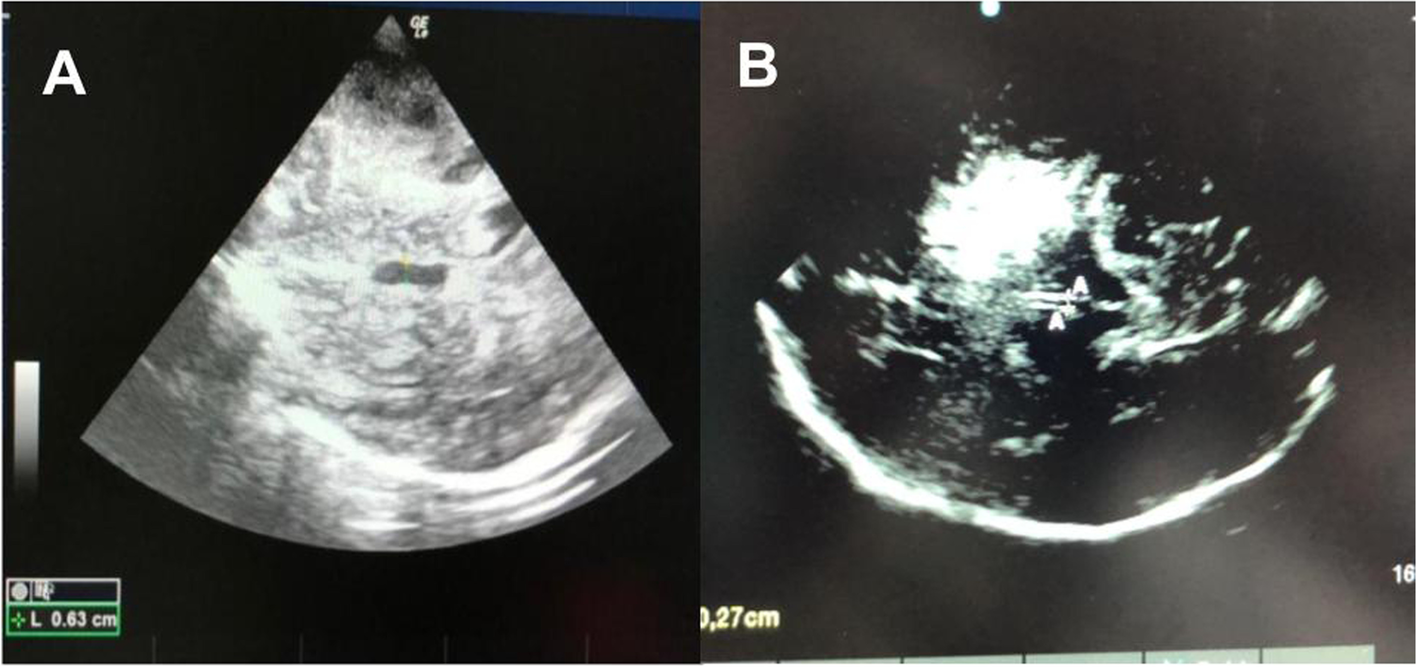

Fig. 4

A The Nerve optic measured through the transorbital window. B ONSD is measured 3mm behind the globe, using an electronic caliper and an axis perpendicular to the optic nerve

Technique

The ultrasound probe (linear probe) should be placed on the temporal area of the eyelid (Fig. 4). The probe should be then angled in order to display the optic disc and the entry of the optic nerve into the globe. ONSD is measured 3mm behind the retina, using an electronic caliper and an axis perpendicular to the optic nerve (Fig. 4). It is paramount to perform a short examination duration and minimize image information loss by recording an US video clip to reduce the examination duration for the safety of the patient, ALARA principle (as low as reasonable achievable) [44]. It is important to reduce the power output of the US, usually expressed as a percentage.

To reduce errors, it has been suggested to use the mean of three values obtained from each patient, for each eye. Furthermore, identifying the main structures (optic nerve, retina, meninges) and following the CLOSED protocol help to improve the inter- and intra-rater reliability and decrease the risk of inter-rater bias [44, 45]. At present, ONDS is considered a basic-plus skill [11].

With regard to ONSD measurement, in the vast majority of published studies, ONSD is defined as the distance between the external borders of the hyperechogenic area surrounding the optic nerve, which represents the subarachnoidal space including the arachnoid mater. In some studies, however, the ONSD was also measured including the outer hypoechogenic rim, which represents the dura mater, resulting in a large heterogeneity of reported reference values [20, 22].

The cutoff of ONDS is another lack in the literature. An ONSD >5.8 mm indicates increased ICP with a sensitivity of 90% and a specificity of 84%; however, the cut-off value is divergent in literature (Table 2), and recent guidelines suggest a threshold ≥ 6.0 mm [5].